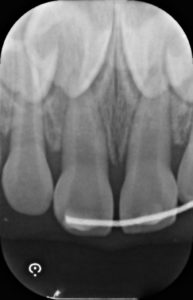

受傷から8ヶ月後

脱臼した歯の色は周囲と殆ど同じくらいに戻りました。

レントゲン所見も異常はないため、追加の処置等は行わず治療終了としました。